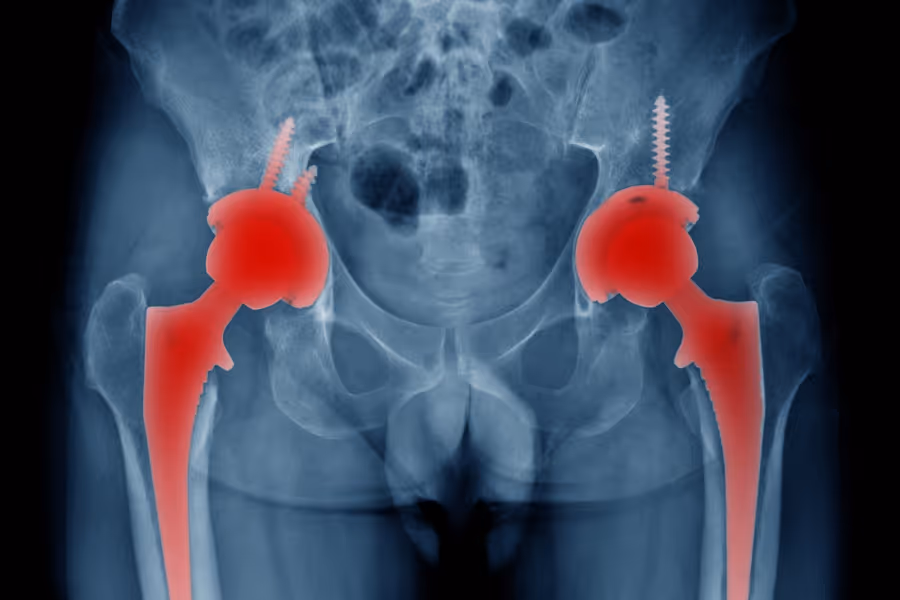

Revision hip replacement (also called revision total hip arthroplasty) is a surgery to repair or exchange parts of an artificial hip joint that have failed.

Think of a hip replacement like the tires and suspension on a car. Over many years (or due to complications), parts can wear down, loosen from the bone, or move out of alignment.

When a hip replacement fails, it hurts to walk, limits your life, and can damage the bone if left untreated. Revision surgery aims to stop the pain, protect the remaining bone, and get you moving again.